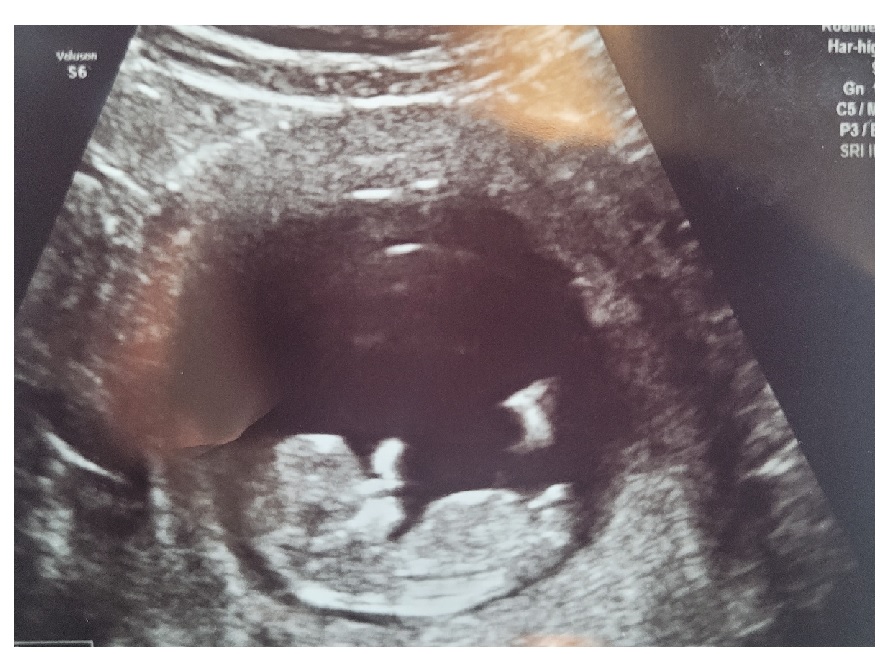

These are my ultrasound pics from yesterday. Measuring 11weeks 5days. I know it is early, but I would love to hear nub predictions.

Attachment 42972